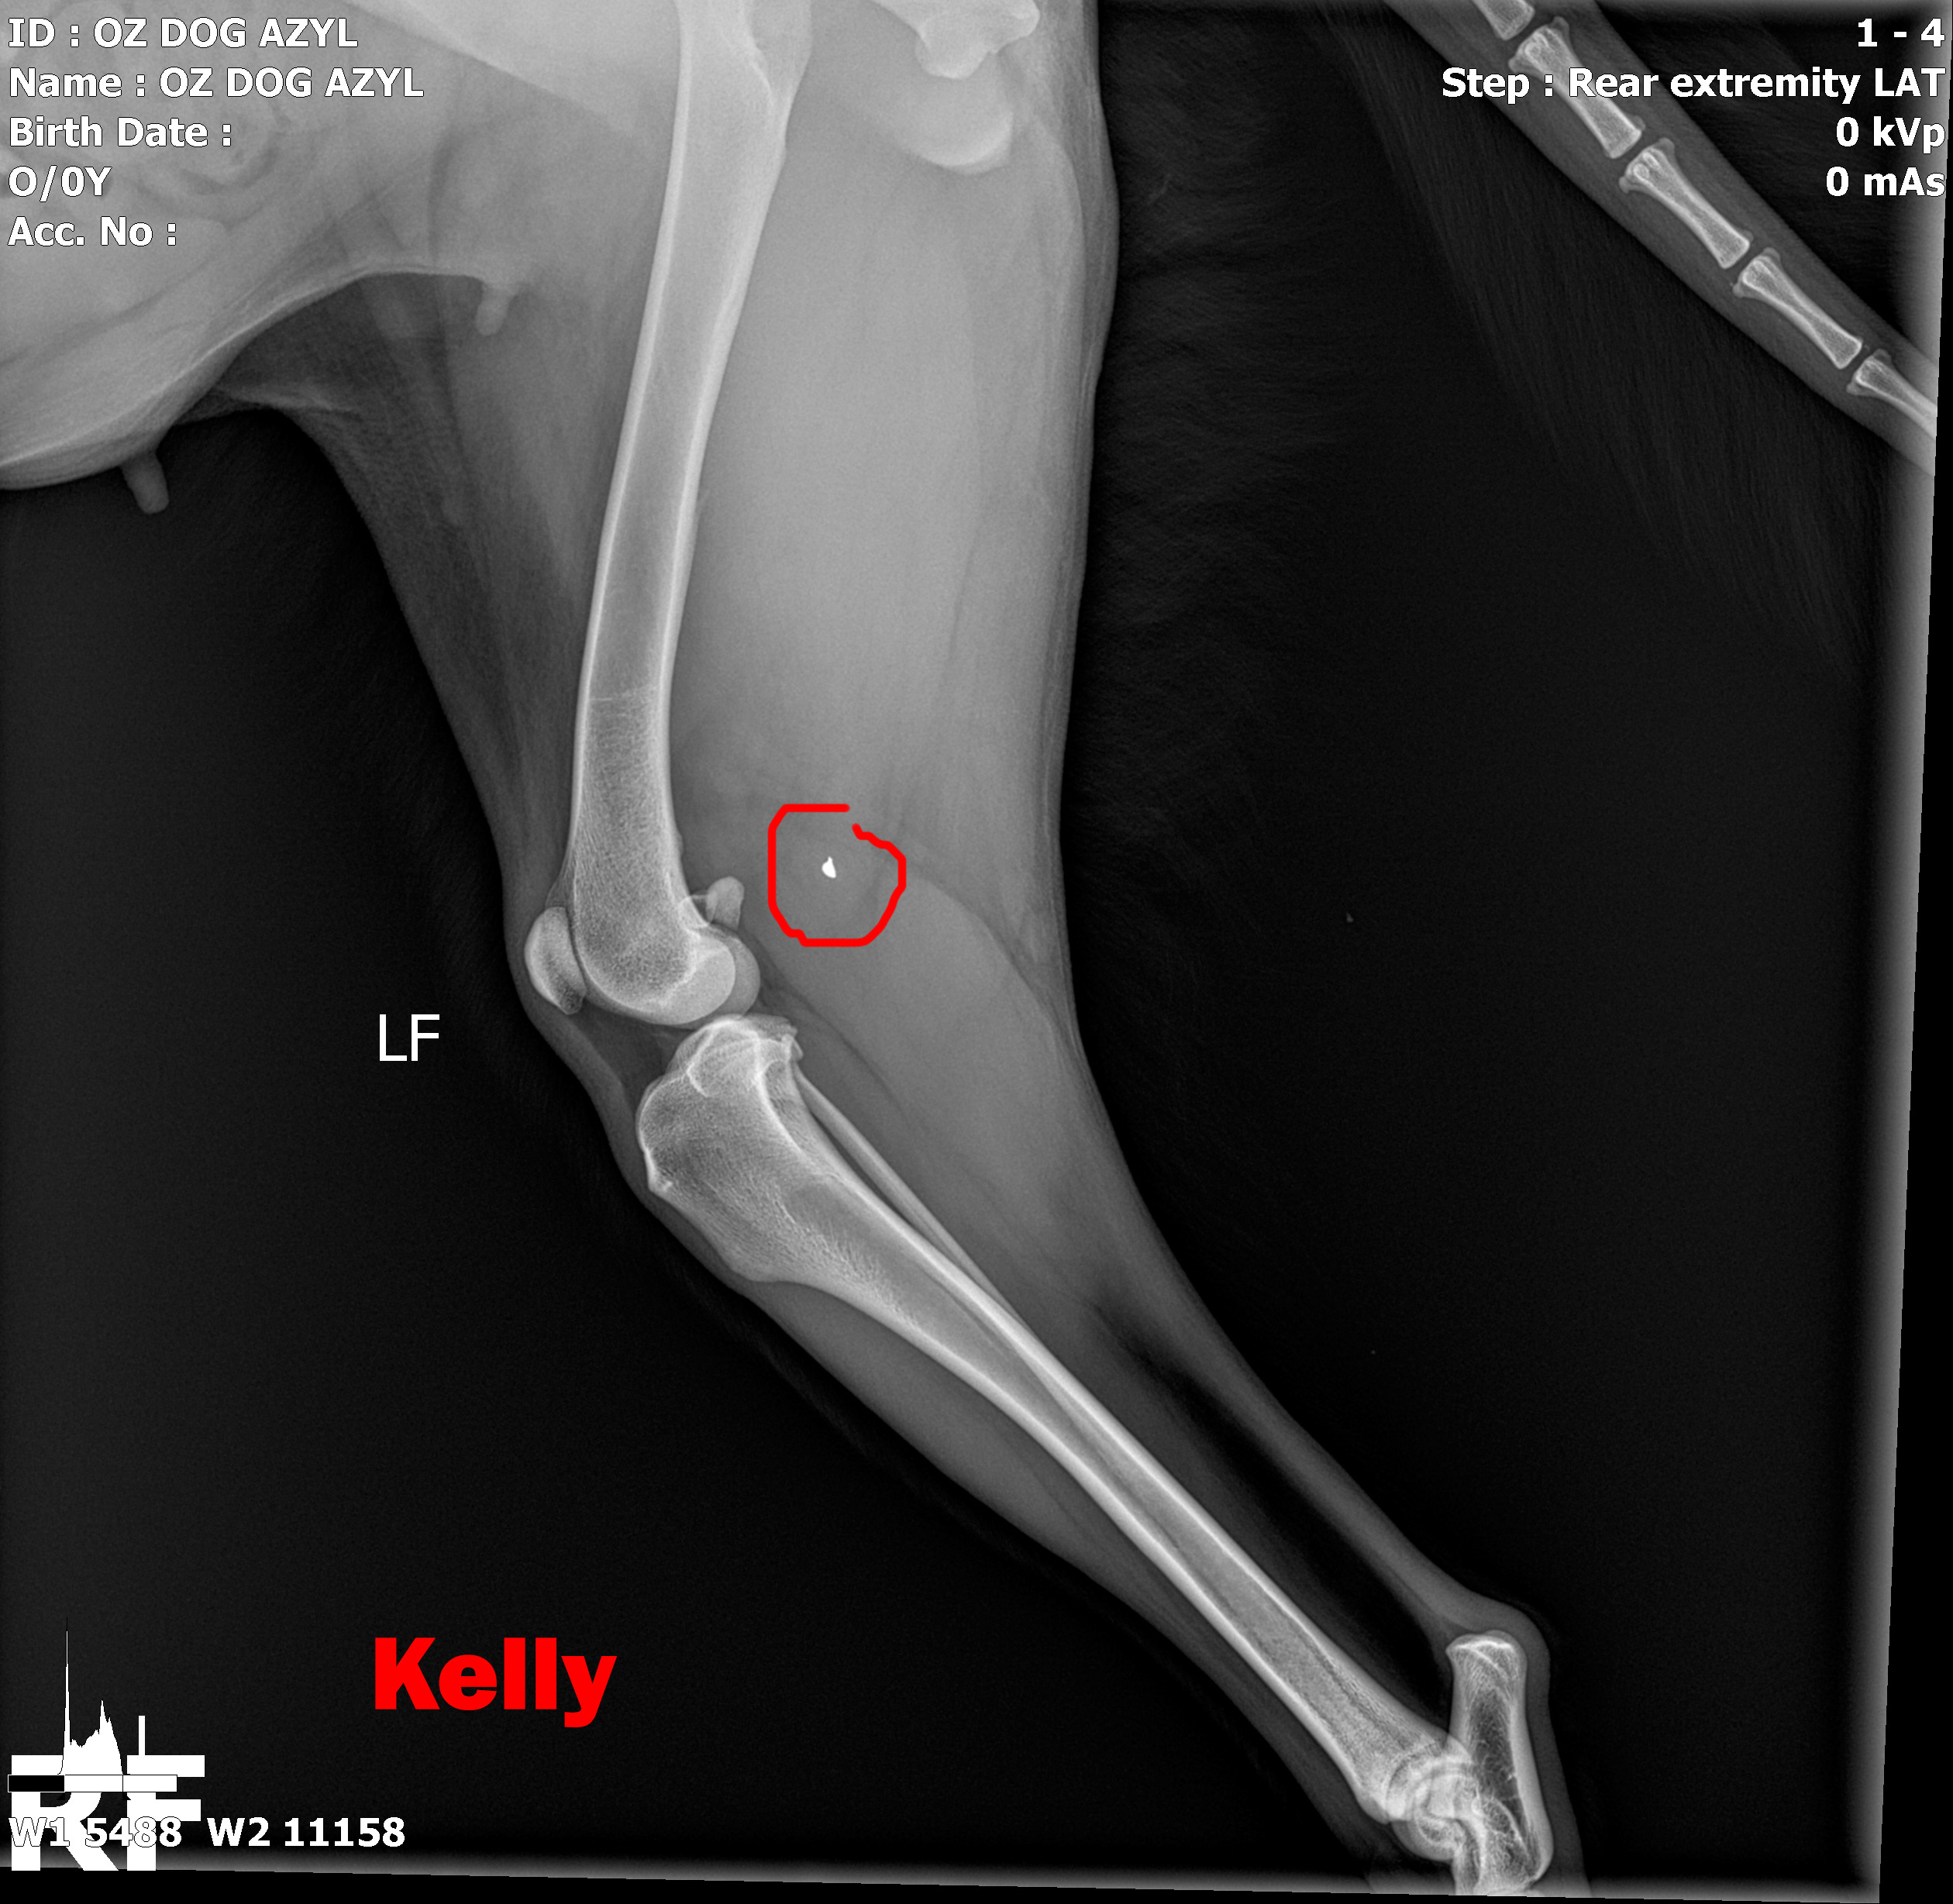

KELLY - Vzali sme ju z ranča, kde boli zvieratá v hororových podmienkach. Neudrží sa na zadných nohách. Môže to spôsobovať hneď niekoľko faktov.

V ľavej packe, medzi druhým a tretím prstom mala brok...

V ľavej packe, medzi druhým a tretím prstom mala brok (treba si to predstaviť, ako keď máte kamienok v topánke a nech stúpate akokoľvek, vždy Vás tlačí. Lenže to je len kamienok a nie cudzí predmet v živom tkanive. Tú bolesť si radšej ani nepredstavujte.) V tej istej nožičke, v oblasti zadnej strany kolena bol ďalší brok, ktorý jej tiež prekážal pri narovnaní nohy. Prvým krokom bolo odstránenie týchto dvoch brokov, ktoré pravdepodobne spôsobovali najväčšie ťažkosti. Operácia sa konala 10.5.2020, dopadla výborne, Kelly sa zotavuje.

Píšeme ale "pravdepodobne" preto, lebo Kelly má tiež problém s krížovým väzom v kolene, ktorý má známky deformácie a má tiež hypointenzitu disku (to znamená, že má na platničke medzi stavcami pruh, ktorý vyčnieva a tlačí na miechu). Veríme, že vsetci strážni anjeli pri nej budú stáť a zvládne sa zotaviť, aby si mohla užívať taký život, aký mala žiť od narodenia. My sme pri nej, zabezpečíme jej všetko potrebné! Za diagnostiku, MRI a chirurgiu máme dve faktúrky, v celkovej výške 762,05€.